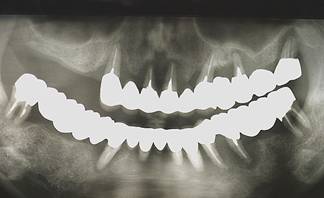

術前パノラマレントゲン写真。根の周りが黒くなり、骨がなくなっていることがわかります

治療後。歯周病で失われた骨が回復しています。使用インプラントはスプラインツイストです。